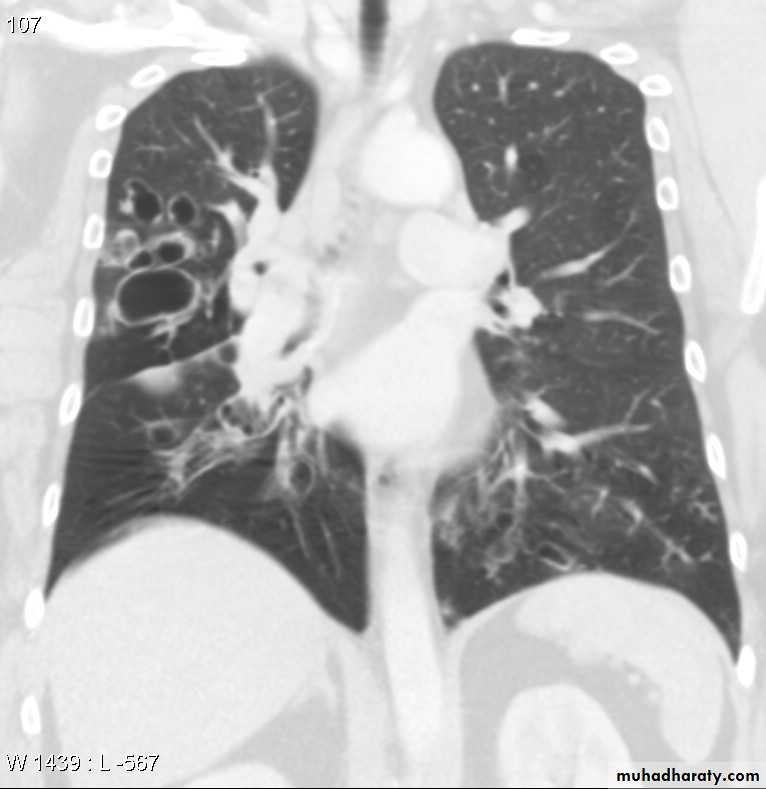

EmphysemaCT scan in Emphysema

High-resolution CT is the most sensitive and specific technique for detection of pulmonary emphysema and grading of its severity.

It is not recommended for routine clinical assessment of COPD, it may be used to evaluate the feasibility of lung volume reduction surgery.